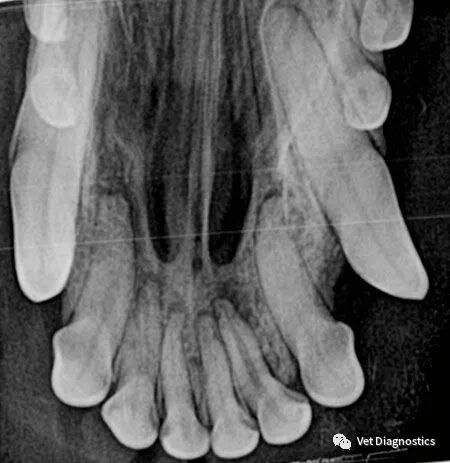

从牙冠上刮除牙菌斑和牙石,并探测牙槽,仅此而已。患者至少有60%的牙齿位于牙龈线以下。口腔内放射照片对于帮助您评估这些区域至关重要(图3A-3D)。

图3B.图3A中增大的根管和根尖周透明与犬患者的一颗非活牙相一致;需要进行根管治疗或拔除。